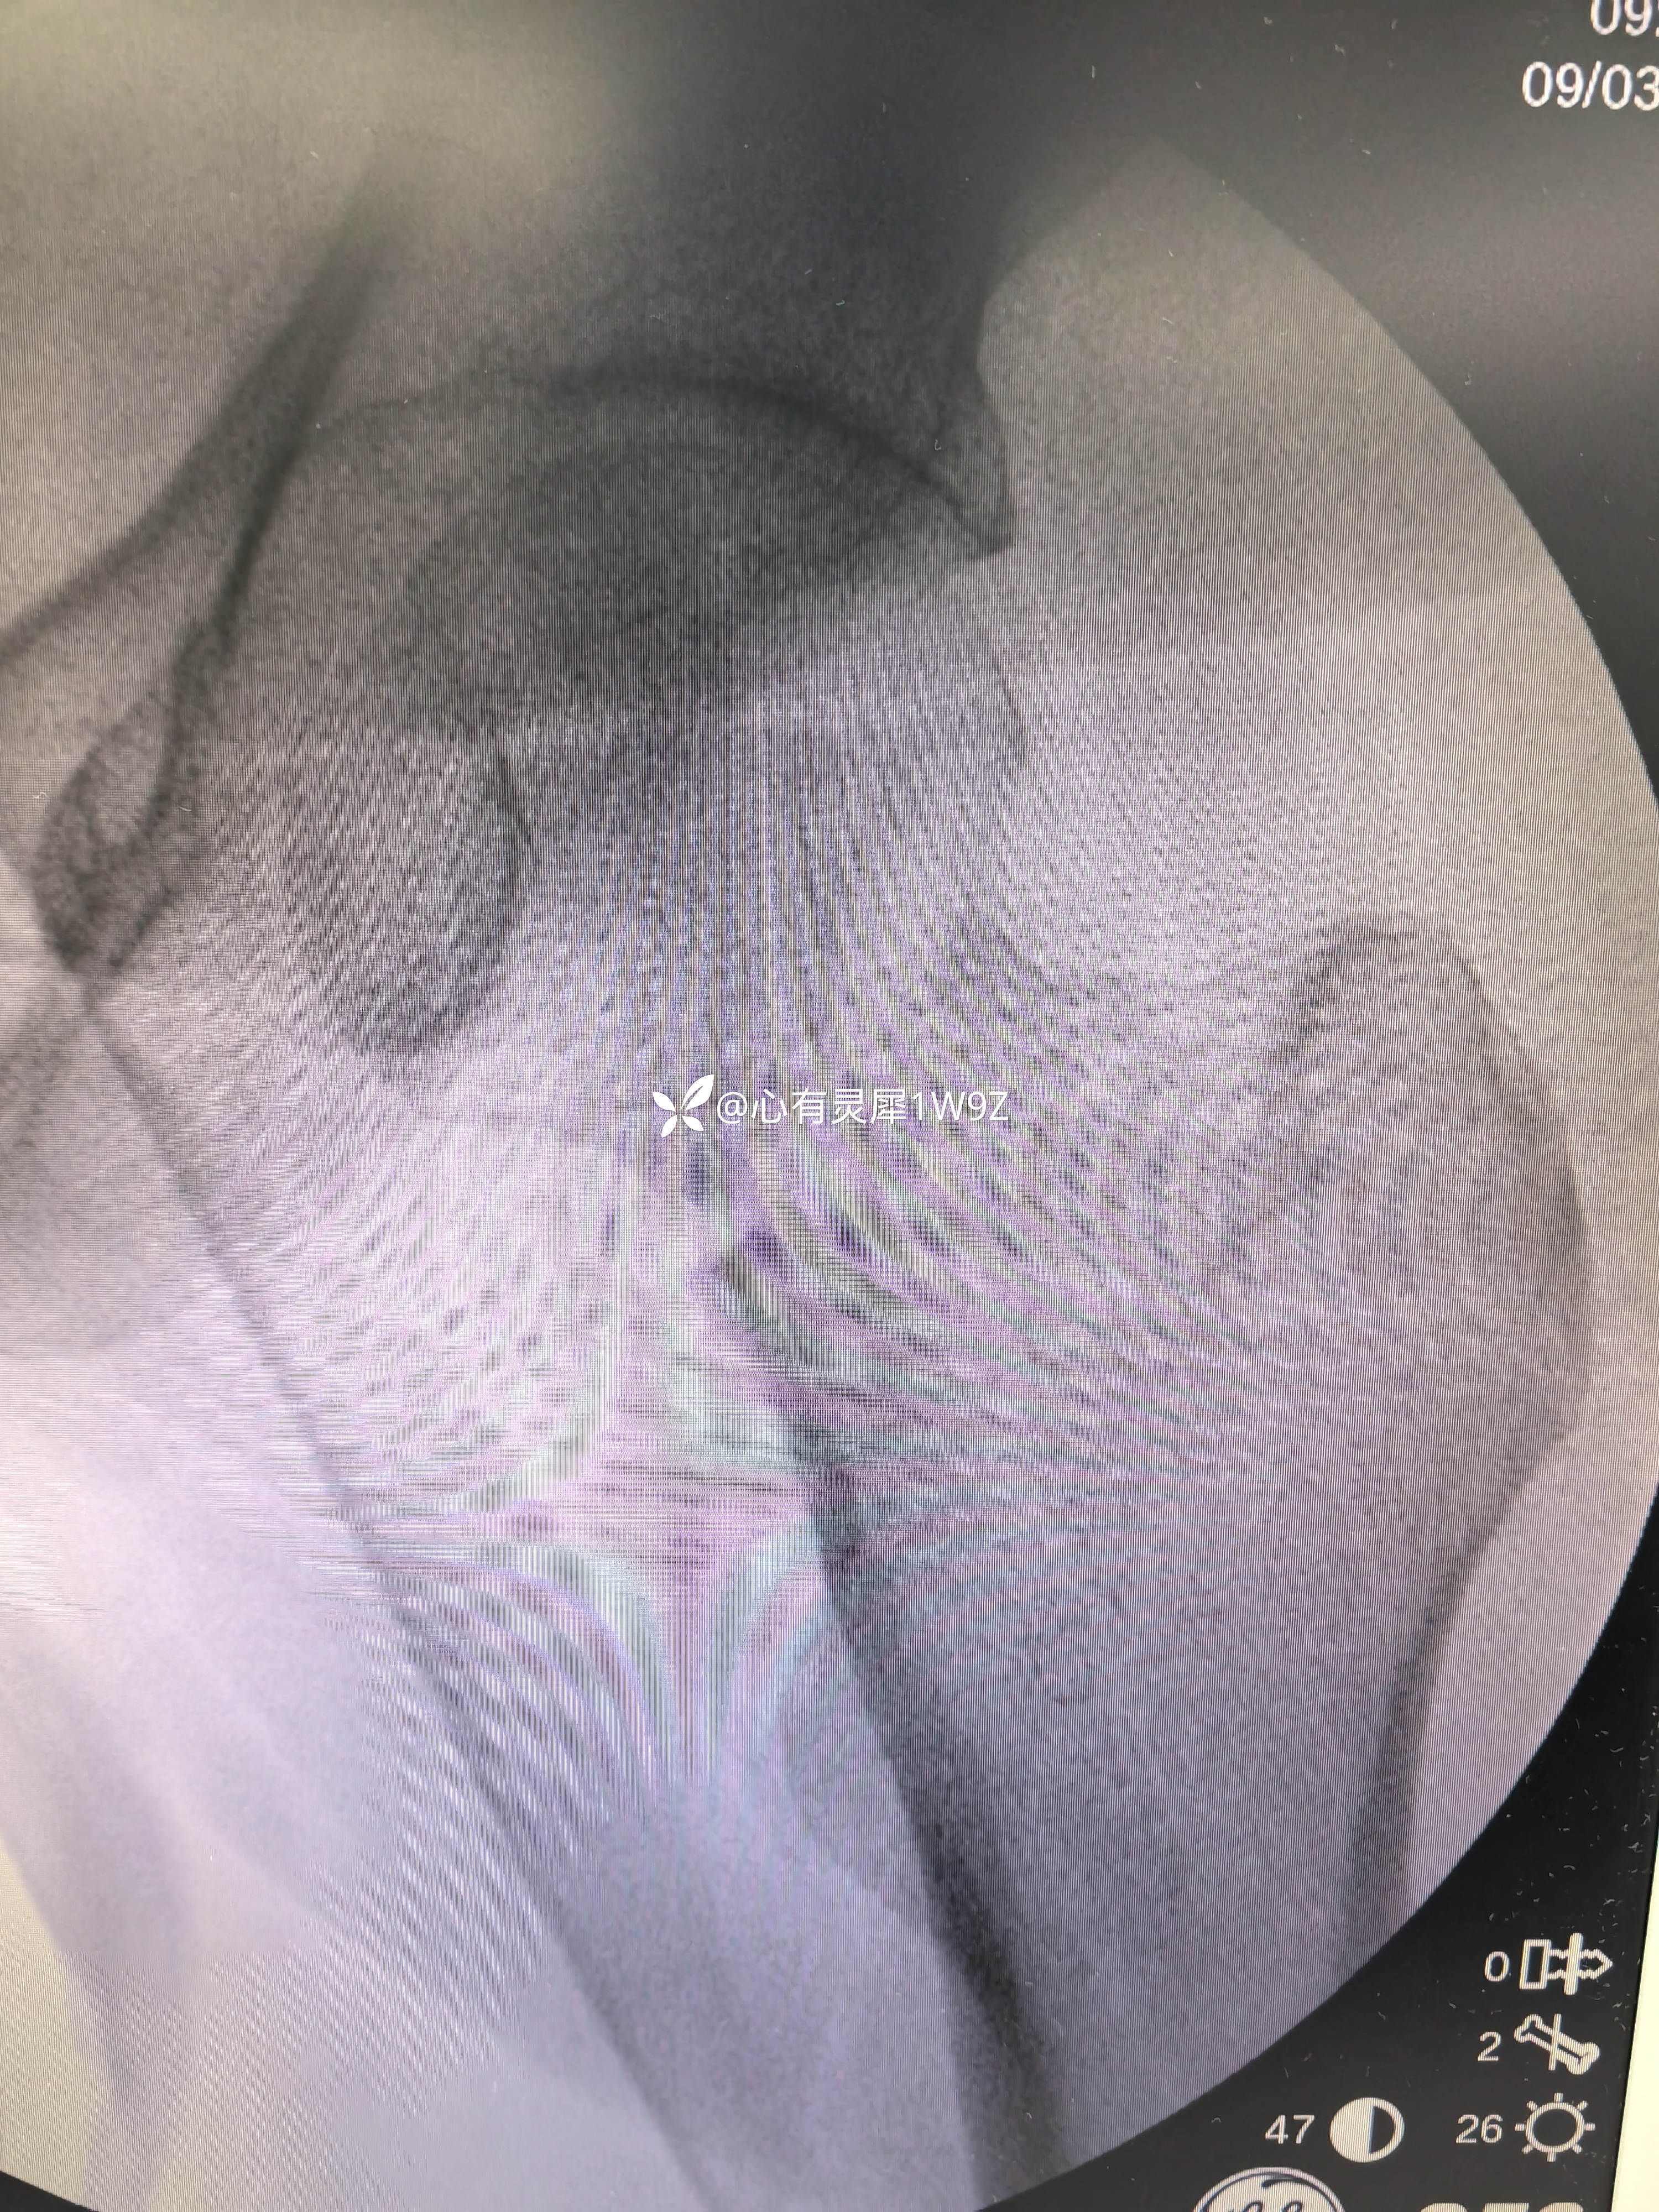

诊断:左侧股骨颈骨折(头下型)garden IV型

1,关于闭合复位的一些经验,该患者牵引床,先外旋外展牵引解锁后透视正位,根据情况再调整牵引内旋透视复位侧位。最后再内旋内收定位画线。